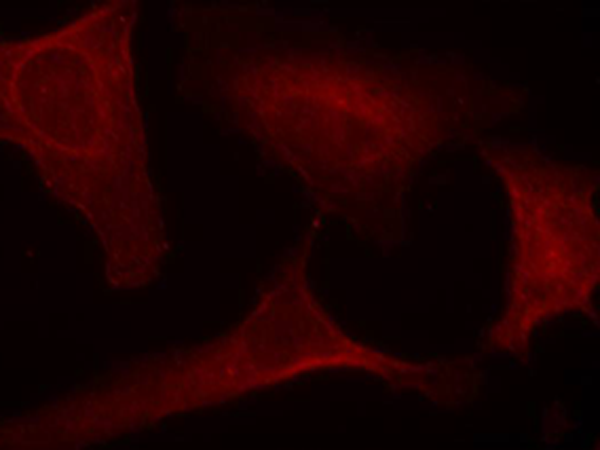

IF Positive control:

Hela cells

IF Recommended dilution

100-200